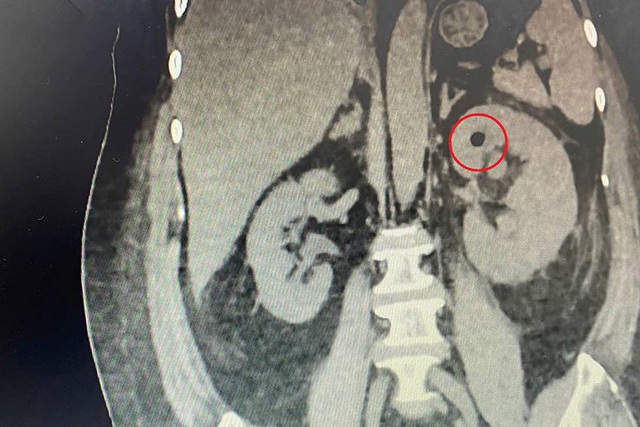

Hình ảnh chụp CT của bà D. cho thấy đốm khí xuất hiện ở thận trái

Ngay trong đêm, người bệnh được chụp CT, kết quả cho thấy xuất hiện hình ảnh đốm khí ở thận trái. Lập tức, các bác sĩ khoa Hồi sức tích cực và chống độc (ICU) đã kết hợp với bác sĩ Trung tâm Tiết niệu - thận học - nam khoa cùng hội chẩn, xác định nguyên nhân gây nhiễm khuẩn huyết của người bệnh.

Kết quả, bà D. được chẩn đoán nhiễm khuẩn huyết từ đường tiết niệu; viêm thận và bể thận trái sinh khí, có sỏi niệu quản trái đoạn chậu gây giãn niệu quản trên dòng, ứ nước thận độ 1 và sỏi nhỏ ở thận trái; tiểu đường loại 2 kiểm soát kém.